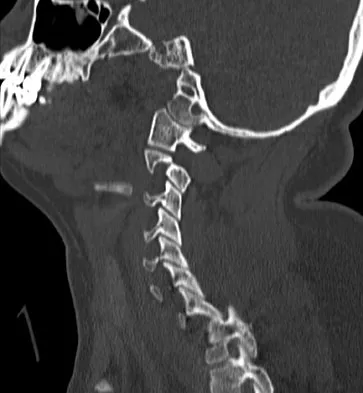

Subluxation caused by rheumatoid arthritis is most commonly seen at what level of the cervical spine?

Explanation

Approximately 65% of cervical subluxations occur at C1-C2. Of these, 50% are anterior, with the remainder being lateral and posterior. The second most common type is basilar invagination, occurring in 40% of patients. The third most common type is subaxial, occurring in 20% of patients with rheumatoid arthritis. Subluxation at more than one level is common. Boden S, Clark CR: Rheumatoid arthritis of the cervical spine, in Clark CR (ed): The Cervical Spine, ed 3. Philadelphia, PA, Lippincott Raven, 1998, p 693. Boden SD, Dodge LD, Bohlman HH, Rechtine GR: Rheumatoid arthritis of the cervical spine: A long-term analysis with predictors of paralysis and recovery. J Bone Joint Surg Am 1993;75:1282-1297.